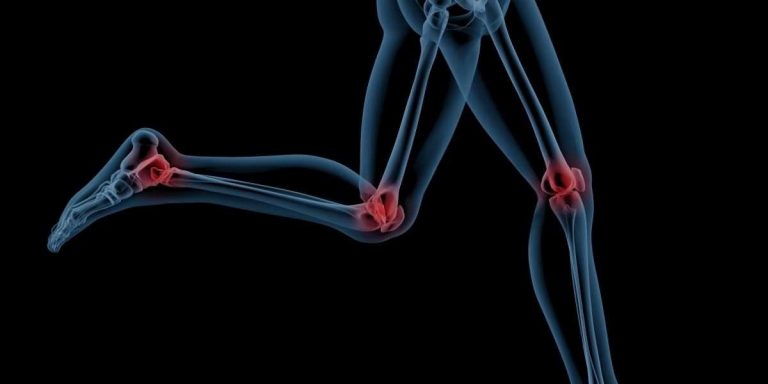

المفاصل تجعل أجسادنا مرنة وتسهل الحركات. هناك العديد من أنواع المفاصل المختلفة الموجودة في أجزاء مختلفة من الجسم وتكون مسؤولة عن الإجراءات المختلفة. هذه المفاصل هي مفصل السرج، المفصل المحوري، المفصل المفصلي، المفصل الثابت، المفصل الإهليجي، المفصل الكروي والمقبس، مفصل الانزلاق وهو مفصل متحرك قليلاً ومفاصل العمود الفقري.

المنقولة بحرية: تعرف أيضًا باسم المفاصل الزليلية، وتحتوي هذه المفاصل على سائل زليلي يمكّن جميع أجزاء المفصل من التحرك بسلاسة ضد بعضها البعض. هذه هي المفاصل الأكثر انتشارا في جسمك، وتشمل أمثلة المفاصل الركبة والكتف.